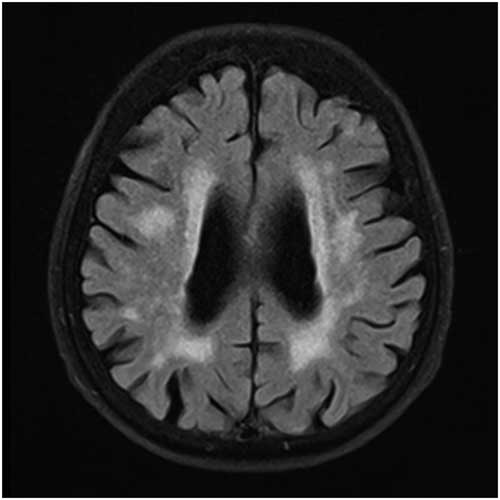

Periventricular WMH was graded in a 0-4 range based on the WMH identified as continuous, confluent areas of high signal intensity adjacent to anterior or posterior horns of the lateral ventricles and along the ventricular system on FLAIR (TR=8000 ms, TE=80 ms, 3 or 5 mm slice thickness, 0.6 mm gap) images.

Subcortical WMH was graded in a 0-4 range based on the WMH identified as lesions located in the white matter but not touching the periventricular area on FLAIR (TR=8000 ms, TE=80 ms, 3 or 5 mm slice thickness, 0.6 mm gap) images.

Details of the proposed scale are given in Table 1. For grading the SA, VA, and MTA, a reference data set was created from cranial MRIs of 30 subjects who were admitted to the clinic owing to complaints other than forgetfulness, but they were not included in the study (Figures 1–3). An exemplary MRI scan of a patient graded with PWMH=4 and SCWMH=3 can be seen in Figure 4.

Figure 4 MRI of a patient with PWMH=4 and SCWMH=3.